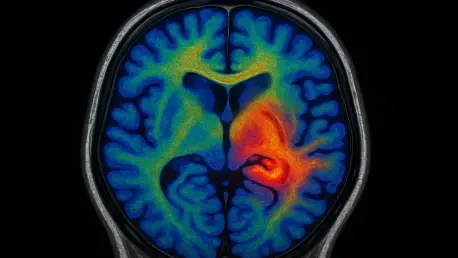

In a landmark investigation detailed in Biological Psychiatry: Cognitive Neuroscience and Neuroimaging, researchers analyzed the brains of 99 World Trade Center responders, roughly half of whom had been diagnosed with chronic PTSD. To peer into the microstructural integrity of their brains, the scientific team employed a highly specialized MRI-based technique known as gray-white contrast (GWC) neuroimaging. This sophisticated method goes beyond simply measuring the size or activity of brain regions; instead, it assesses the sharpness and distinctness of the boundary separating the brain’s gray matter from its white matter. In a healthy brain, this boundary is crisp and well-defined, reflecting an orderly and efficient architecture. Gray matter, dense with neuronal cell bodies, is primarily responsible for information processing, while white matter, composed of myelinated nerve fibers, acts as the brain’s communication network, transmitting signals between different regions. A clear demarcation between these two types of tissue is crucial for optimal neural function and signaling speed.

The selection of gray-white contrast neuroimaging was pivotal, as it provides a unique window into the brain’s fundamental structure that other common imaging modalities might miss. Unlike functional MRI (fMRI), which measures blood flow to infer brain activity, or standard structural MRI, which assesses the volume of different brain areas, GWC analysis offers a direct measure of tissue integrity at a microscopic level. A blurry or indistinct border, as identified by GWC, suggests a pathological change in the composition of the tissue itself, indicating that the normal architectural separation has been compromised. This approach allowed researchers to detect subtle but widespread abnormalities that are not about a brain region shrinking or becoming overactive, but about the very nature of the tissue changing. This level of detail is critical because it moves the focus from macroscopic changes to the underlying cellular and structural health of the brain, offering a more fundamental understanding of how severe trauma can physically reshape the organ responsible for our thoughts, emotions, and memories.

The Blurring Lines of Neural Matter

The study’s central and most startling discovery was a significant and widespread reduction in the distinctness of the gray-white matter boundary among the responders with chronic PTSD. This low GWC value indicates that the gray matter in these individuals had taken on characteristics more typical of white matter. The researchers theorize that this blurring is caused by an abnormal concentration of myelin—the fatty, insulating sheath that normally envelops the axons of white matter—infiltrating the gray matter regions. This structural anomaly suggests a profound disruption in the brain’s organization, potentially impairing its processing speed and consistency. The integrity of the gray-white matter boundary is essential for efficient neuronal signaling, and its compromise could explain many of the cognitive and emotional difficulties experienced by those with PTSD. The fact that these changes were not confined to a single, isolated brain region but were observed across the cortex underscores the pervasive and systemic impact of severe trauma on the brain’s physical architecture.

Further analysis revealed a powerful and specific link between the degree of boundary blurring and the severity of a particular cluster of PTSD symptoms: re-experiencing. This category includes the disorder’s most hallmark and intrusive symptoms, such as debilitating flashbacks, nightmares, and involuntary, distressing memories of the traumatic event. The strong correlation suggests that the observed physical changes in the brain’s structure are not just a general marker of the disorder but may be directly tied to the neural mechanisms that cause traumatic memories to be replayed against a person’s will. This finding is exceptionally important because it provides a tangible, biological explanation for one of the most painful and disorienting aspects of living with PTSD. By connecting a specific, measurable brain abnormality to a core subjective experience, the research strengthens the argument that PTSD is a neurological injury, not just a psychological reaction, and provides a clear target for future research into treatments that could potentially reverse or mitigate these structural changes.